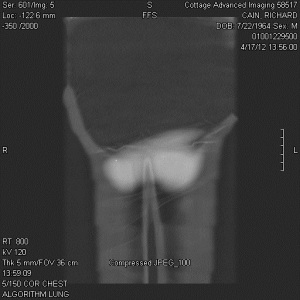

“My family and I have been the subjects of Government funded human research and/or hate crimes. These crimes are being covered-up by using the words National Security. The fact that my two minor children have the same and/or similar devices in their little bodies speaks for themselves. My sons were ages 3 and 4 when the discoveries took place. Their x-rays, blood & urine analysis present the true facts. The devices can only be introduced into the body, while being in a medical facility. All three of us were patient of the same defendant hospital.

“The CD-ROM from CCAI depicts the same images that are attached. I will bring the 01/03/2012 Simonmed Imaging CT scan which also depict foreign objets in the heart and chest.”

“Please take a look at both X-rays. Superimpose the foreign objects AKA EKG clamps and you will find that they are the same devices. when have you ever seen an EKG clamp place sideways in the abdomen? Both x-rays have been confirmed by Radiologist Louis Teresi as having foreign body reactions in the abdomen, right and left flanks.

“The obvious implant in the 2012 x-ray stands out from the others, because it at the time had not embedded into my flesh (heart).”